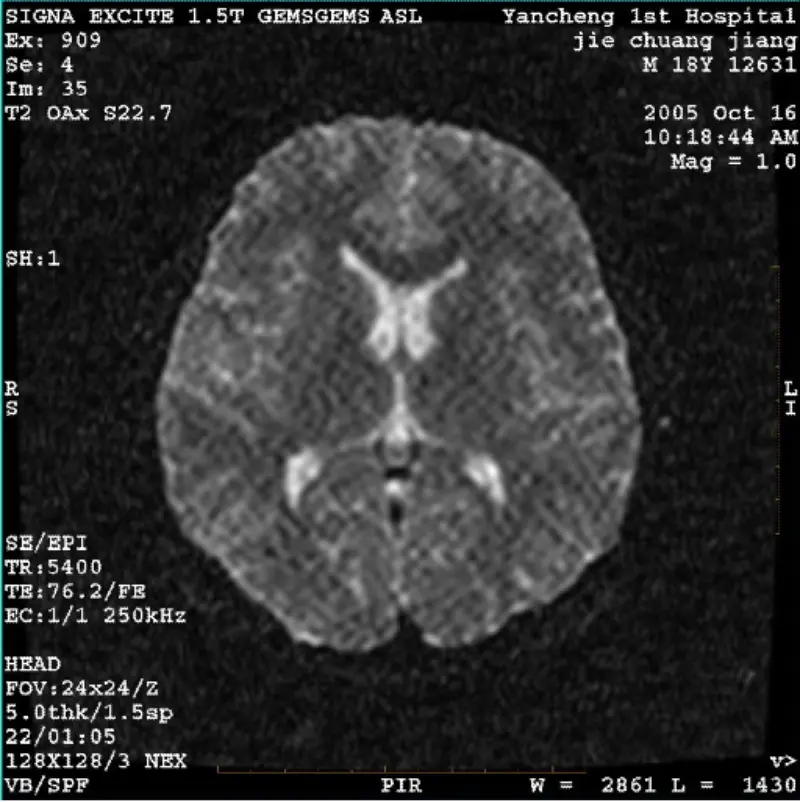

consulte Mais informaçãoSISTEMA: 1.5T Signa Twin Excite II (versão de software 11.0M4) PROBLEMA/SINTOMA Imagem DWI (modo Zoom e modo inteiro) e fiesta (modo zoom e modo inteiro) tendo artefato visível de reticulado ou veludo cotelê, independentemente do uso de bobina corporal ou cabeça bobina, outra imagem de rotina......